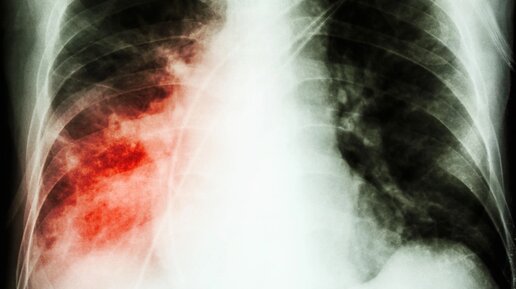

Проверить пневмонию можно в домашних условиях. Для этого необходимо обратить внимание на симптомы, которые могут проявляться остро или же постепенно. Пневмония – воспалительное заболевание лёгких. Оно может быть вызвано вирусами и бактериями. Как правило, болезнь развивается и прогрессирует на фоне снижения иммунитета. Внешне она напоминает по своей симптоматике грипп, ОРВИ и другие подобные заболевания. Но последствия без правильно подобранного лечения могу быть серьёзными. Поэтому очень важно разобраться, как проверить пневмонию в домашних условиях и не пропустить первых симптомов болезни...

Застойная пневмония - одно из самых грозных осложнений у лежачих пациентов. Разбираемся, по каким симптомам можно ее быстро выявить и как предупредить развитие воспаления легких. В прошлой статье мы разобрались, почему пневмония часто бывает у лежачих больных, даже если они не простужались и не контактировали с инфицированными людьми. (Спойлер: механизм застойной пневмонии у лежачих больных связан с пассивным переполнением венозных сосудов вследствие нарушения оттока крови). Теперь поговорим, как вовремя заметить и не допустить развитие этого осложнения...